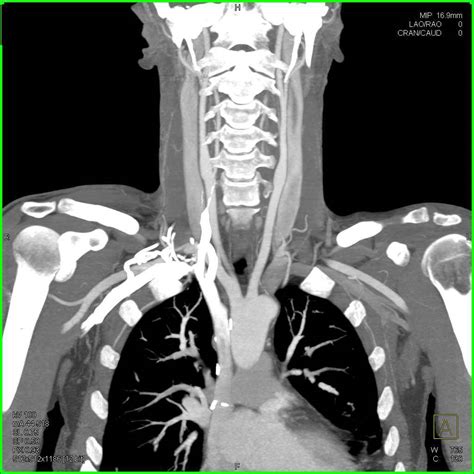

A CT scan of neck, often referred to as computed tomography, is a sophisticated diagnostic imaging procedure that utilizes X-rays combined with computer processing to create detailed, cross-sectional images of the structures within your neck. Whether your physician is investigating a persistent lump, evaluating unexplained pain, or monitoring a known condition, this imaging tool provides a level of clarity that standard X-rays cannot match. By capturing slices of the neck’s anatomy—including the thyroid gland, lymph nodes, blood vessels, and spinal structures—doctors can pinpoint abnormalities with remarkable precision, making it an essential component in modern diagnostic medicine.

The technology behind a CT scan of neck is fascinating. The patient lies on a motorized table that slides into a large, doughnut-shaped scanner. As you move through the scanner, an X-ray tube rotates around you, sending thin beams of radiation through your body. Detectors on the opposite side of the scanner record these beams, and the computer processes this information to create detailed, 3D-like images of the internal structures.

In many cases, the radiologist may decide that a contrast dye is necessary to enhance the visibility of specific tissues, blood vessels, or abnormalities. This contrast material, usually iodine-based, is typically injected into an intravenous (IV) line in your arm before the scan begins.